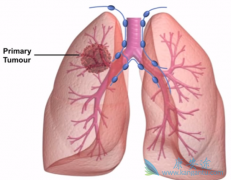

• 厄洛替尼(ERLOTINIB)联合阿瓦斯丁治疗EGFR突变的肺癌患者有效吗

厄洛替尼(ERLOTINIB)联合阿瓦斯丁治疗EGFR突变的肺癌患者有效吗

表皮生长因子受体酪氨酸激酶抑制剂(EGFR-TKI)可有效延长EGFR突变的晚期非小细胞肺癌患者的生存期,在EGFR突变的肺癌患者中,EGFR-TKI治疗前,可检测到高达65%患者伴有T790M突变,而T790M突变通常与缩短的PFS相关。BELIEF是一项II期单臂、多中心研究, ...

• 特罗凯/厄洛替尼对脑转移瘤的控制比其它一二代药物更好

特罗凯/厄洛替尼对脑转移瘤的控制比其它一二代药物更好

目前肺癌的治疗已进入精准医学时代,靶向药物非传统的肺癌治疗带来了巨大改变,对于有相关基因突变的患者,可直接选择相应的靶向药物治疗,不用在承受传统疗法的痛苦。 特罗凯 (厄洛替尼)作为二代EGFR-TKI,在肺癌治疗中的疗效和安全性表现如何呢?安 ...